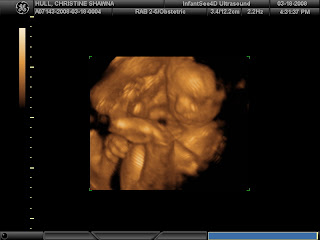

So here she is folks, Ainsleigh Madelynn

And here’s a face shot, not the best because she was so close to the placenta that there wasn’t enough fluid by her face to get too many great shots